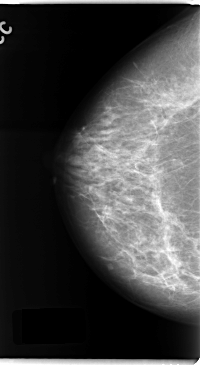

C_0137_1.RIGHT_CC

RIGHT_CC LINES 4744 PIXELS_PER_LINE 2600 BITS_PER_PIXEL 12 RESOLUTION 50 NON_OVERLAY